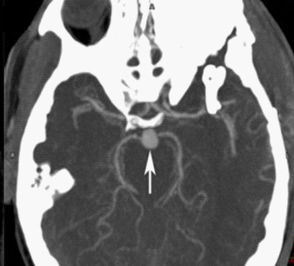

我们使用CT或MRI造影,都能发现动脉瘤的存在。下图这个箭头指的圆圆的、和周围血管不一样的地方就是动脉瘤。

CTA提示基底动脉尖动脉瘤 图源:WestJEM